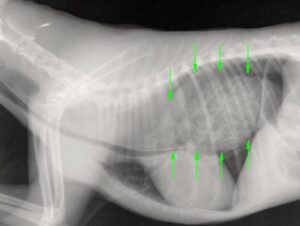

Wijd openstaande verlamde slokdarm (megaoesofagus)

Bij regurgiteren is verder onderzoek belangrijk. Afhankelijk van eventuele andere klachten kan dit bestaan uit röntgenfoto’s van de thorax (om te evalueren voor een megaoesofagus en PRAA, maar ook de complicatie van een longontsteking), een echo van de buik, bloedonderzoek en in sommige gevallen een slikfilm. Een verwijzing naar de internist kan nodig zijn voor een behandelplan op maat.